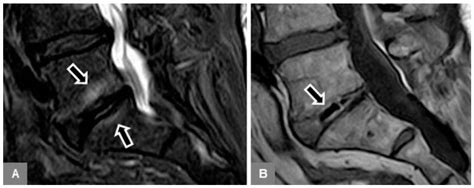

Diagnosing Modic Type 1 Endplate Changes requires high-quality MRI imaging. Because these changes involve fluid and bone marrow, standard X-rays or CT scans are generally insufficient to see the soft-tissue-like inflammation. An MRI provides the necessary detail to differentiate between the active inflammatory state of Type 1 and the more stable, chronic states of Types 2 and 3.

Physicians will typically look for a "bright" signal on T2-weighted images and a "dark" signal on T1-weighted images at the level of the disc space. While these findings are objective, it is essential for clinicians to correlate these images with the patient's physical symptoms. In some cases, Modic changes can be found in asymptomatic individuals, so a comprehensive clinical exam is always required.